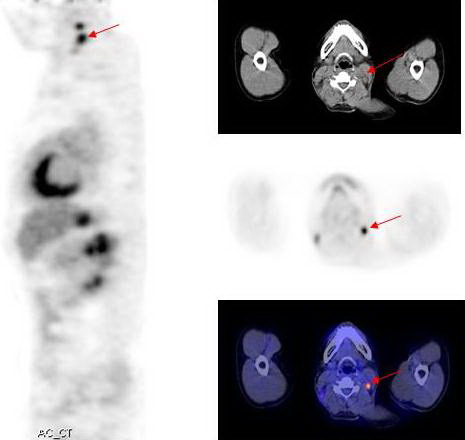

Hình 1: Hình ảnh PET tổng thể cho thấy các tổn thương tăng hấp thu FDG bất thường tại các vị trí mũi tên.

Hình 2c: Hình PET/CT thấy tổn thương tăng hấp thu FDG tại vùng vòm họng bên trái

Kết quả PET/CT: tổn thương tăng hấp thu FDG mạnh tại vòm họng bên trái, max SUV=11,8, các tổn thương di căn hạch tại vùng cổ bên phải và bên trái.

Trong khi đó kết quả nội soi vòm họng và CT không phát hiện thấy tổn thương u nguyên phát (CT-) bởi vì tổn thương ở mức độ chưa xâm lấn ra bề mặt niêm mạc vòm họng và mà mắt chưa thể nhận thấy được  qua  nội soi, CT...

Dựa vào các kết quả trên, bệnh nhân được chẩn đoán là ung thư vòm họng di căn hạch cổ hai bên. Đồng thời đánh giá được giai đoạn bệnh của bệnh nhân là T1N2M0, kế hoạch điều trị tiếp theo là xạ trị phối hợp hoá trị.